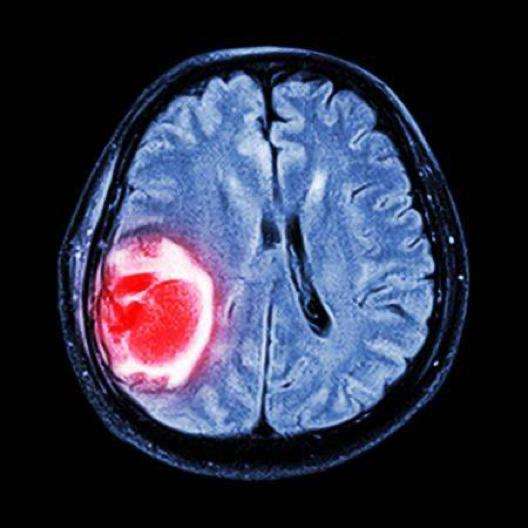

(三甲医院神经外科主治医生 , 擅长脑出血、脑梗死、脑挫裂伤、硬膜下血肿、硬膜外血肿、颅脑肿瘤、脑膜瘤、胶质瘤、听神经瘤、脑积水、颅内感染等脑部疾病 。 欢迎下方留言评论 。 )